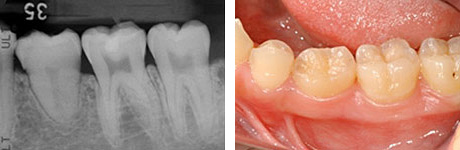

Before

After

17歳、少女。左下の第二小臼歯が生まれつきありません。そこで、右下親知らずの移植を行いました。この症例では、左下の親知らずでもドナー歯として大丈夫ですが、抜歯しやすい右下を選びました。

治療前の写真は乳歯がまだ残っています。